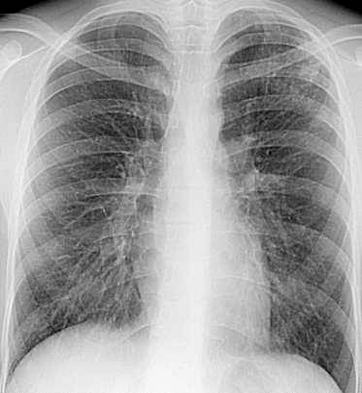

Рис. 2 Очаговый туберкулез легких в фазе петрификации При прогрессировании очагового туберкулеза процесс может выходить за рамки очагового и трактоваться как инфильтративный, кавернозный, ограниченный диссеминированный туберкулез. При благоприятном течении инфильтративного и кавернозного туберкулеза деструктивные изменения в легких могут трансформироваться в очаг размером до 1 см. Подобные очаги нередко имеют радиарно расходящиеся тяжи, т.е. наблюдаются изменения рубцового характера в окружающей ткани. Воротынцева Н.В. подразделяет туберкулёзные очаги на 5 групп - Экссудативные очаги (с перифокальным воспалением) на рентгенограмме представляются в виде округлых или неправильной формы крупных – до 10 – 15 мм. теней с нерезкими контурами, постепенно переходящими в окружающую легочную ткань. При более или менее густом расположении очагов тени их накладываются друг на друга, сливаясь в инфильтратоподобные образования. - Продуктивные очаги – мелкие и средние, обычная величина которых 3 – 8 мм, форма округлая, овальная или неправильная, контуры резкие, структура негомогенная. - Фиброзно-продуктивные очаги размерами 3 – 8 мм., пронизаны фиброзными тяжами. - Казеозно-некротические очаги крупные или средней величены размерами 5 – 15 мм., округлые, с резкими контурами, различной структуры; морфологически отличающиеся от туберкулом только меньшими размерами. - Кальцинированные – очаги любых размеров, содержащие соли кальция. При активном туберкулёзе обнаруживаются первые 4 варианта указанных очагов, а при неактивном – последние 4 варианта. В центре экссудативного или казеозно–некротического очага при томографическом исследовании можно обнаружить мелкие участки деструкции. Эти, так называемые, кавернизированные очаги могут быть источником бацилловыделения. Окружающая легочная ткань при очаговом туберкулёзе чаще всего содержит патологические элементы в виде: – изменения легочного рисунка; – деформации и нерезкости сосудистых тяжей (перибронхиальное и периваскулярное воспаление); – мелкоячеистой сетки с нечеткими трабекулами в зоне поражения (перилобулярное воспаление); – интерстициального фиброза – крупноячеистая перестройка легочного рисунка с четкими трабекулами, между которыми видны просветления в виде розеток; – усиленного и сгущённого рисунка – сосудистые тени не истончаются постепенно, а на всем протяжении имеют одинаковую толщину и резкие неровные контуры; – обрывов и перегибов сосудистых теней. Чем больше выражен фиброз, тем медленнее наступает обратное развитие свежих воспалительных изменений и тем вероятнее возможность рецидива в будущем. Очаговый туберкулез обычно протекает доброкачественно, часто бессимптомно или с малыми клиническими проявлениями. Для этой формы туберкулеза характерно волнообразное течение со сменой фаз обострения и затихания. Но даже в период вспышки этой форме присуще отсутствие ярких клинических проявлений. Это значит, что больные очаговым туберкулезом могут не знать о своей болезни и поэтому не обращаться за медицинской помощью. Очаговый туберкулез легких в большинстве случаев имеет тенденцию к самоизлечению или хроническому течению. Вновь образованные очаги под влиянием адекватной антибактериальной терапии в течение 1,5–2,5 мес. могут полностью исчезнуть. Однако в подавляющем большинстве излечение вторичных очаговых форм происходит по «дефектному типу» с остаточными изменениями в ткани легкого. Трудности обнаружения и правильной интерпретации этой формы туберкулеза в значительной мере связаны с суперпозицией очаговых теней с костным скелетом грудной клетки, а именно, с ребрами и ключицей. Даже на линейных томограммах так называемые тени размазывания нередко затрудняют выделение в чистом виде туберкулезных очагов. Более убедительную картину дает компьютерная томография, поскольку на аксиальных срезах очаги уплотнения легочной ткани освобождаются от суперпозиции со стороны костного скелета (рис. 1). Особое внимание следует обращать на пациентов с ограниченными (моно – бисегментарными) изменениями казеозно-некротического характера. У таких больных в пределах одного – двух сегментов (чаще всего в S1 – S2) видны разной величины, негомогенные, иногда частично кальцинированные очаги на фоне более или менее выраженных фиброзных изменений, перифокальной буллёзной эмфиземы и в сочетании с изменениями плевры. Считается также, что к оценке плотности очагов следует относиться с большой осторожностью. Среди рентгенологов и фтизиатров укоренилось представление, будто бы по характеру выявляемых на рентгенограммах очагов можно оценивать степень активности туберкулезного процесса. Между тем рентгенологи знают, что на оптическую плотность очаговых и инфильтративных процессов в рентгенологическом изображении заметное влияние оказывает не столько физическая плотность очагов воспаления или опухолевой инфильтрации, сколько величина очагов, степень заполнения альвеол и состояние воздушности окружающей легочной ткани. При эмфиземе вследствие эффекта вычитания (субтракции) интенсивность очагов уплотнения легочной ткани, проекционно наслаивающихся на гиперпневматизированные, буллезно вздутые участки легкого, снижается вплоть до полного их исчезновения. К.В. Помельцов (1971) отметил, что значительная часть кальцинированных очагов не выявляется на прижизненных рентгенограммах. И наоборот, полутень, обусловленная фиброзной капсулой вокруг кальцинированного центра очага, может восприниматься как перифокальное экссудативное воспаление. Некоторые ученые полагают, что по рентгенологической картине трудно оценивать степень активности туберкулеза. Лучшим показателем, по их мнению, является стабильность рентгенологической картины в течение 6 мес и отрицательные данные исследования мокроты. Исходя из этого, упомянутые авторы рекомендуют рентгенологам вместо описательного термина «неактивного» или «старого туберкулеза» пользоваться термином «рентгенологически стабильный туберкулез». При двустороннем очаговом туберкулезе в некоторых случаях возникают трудности его разграничения с диссеминированным туберкулезом. В связи с этим фтизиатрами принято относить к очаговой форме туберкулезный процесс, охватывающий верхушки легких до переднего конца второго ребра. Большую степень распространения процесса относят к диссеминированному туберкулезу. В затруднительных случаях следует принимать во внимание количество очагов, т.е. степень обсеменения. При наличии множественных густо расположенных очагов в пределах верхних легочных полей двусторонний очаговый туберкулез следует классифицировать как ограниченный диссеминированный. В протоколе рентгенологического исследования при очаговом туберкулёзе рентгенологу необходимо ответить на следующие вопросы: 1. Есть ли очаги в легких, сколько их, где они расположены, их размеры, форма, структура, имеется ли перифокальное воспаление, кальцинированные включения. 2. Состояние окружающей легочной ткани и плевры (интерстициальное воспаление, фиброз, плевральные изменения, буллёзная эмфизема, гипер- или гиповентиляция). 3. Состояние корней лёгких (есть ли кальцинированные лимфатические узлы, признаки повышения давления в малом круге кровообращения, нарушение топики, фиброзные изменения). 4. Состояние диафрагмы.